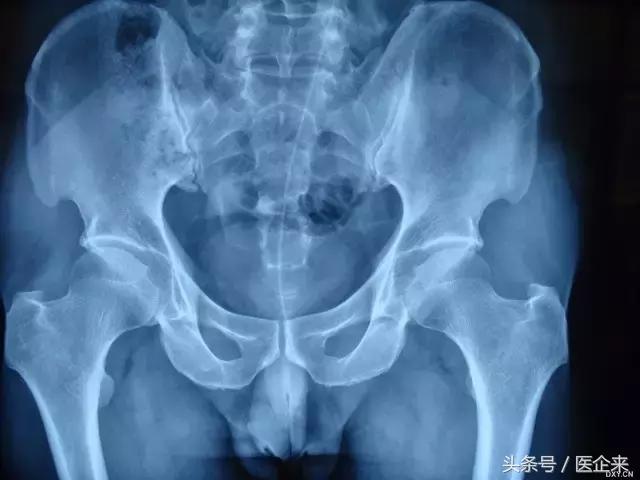

7. 玻璃杯经肛门进入(这是怎么塞进去的?还是不细思这个问题了...)